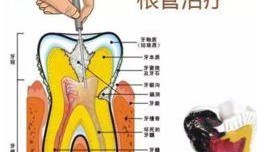

根管治疗视频,从视频学习根管治疗技巧与流程

最近牙疼得我简直要抓狂了!你知道那种感觉吗?就像有一颗小钢珠在你的牙髓里不停地滚动,痛得你连呼吸都小心翼翼。于是,我决定上网搜一...